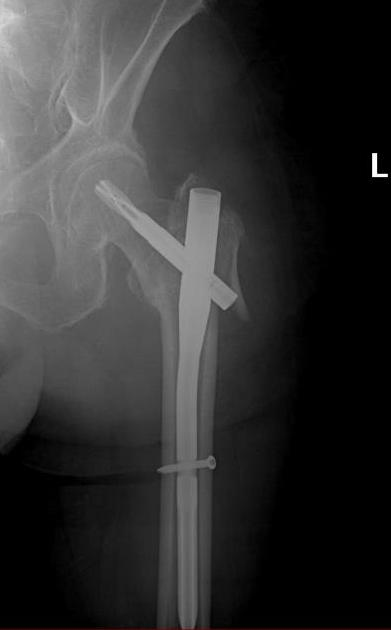

Due to the fact that modern, powerful, easily applicable fixing devices can be placed with minimal incisions to the patients, the prosthesis is not generally applied in the treatment of trochanteric fractures. A convenient pre-surgery planning and the proper application of fixation devices (nails) allow patients to walk in the early stages and protected from the handicaps of prosthetic surgery.